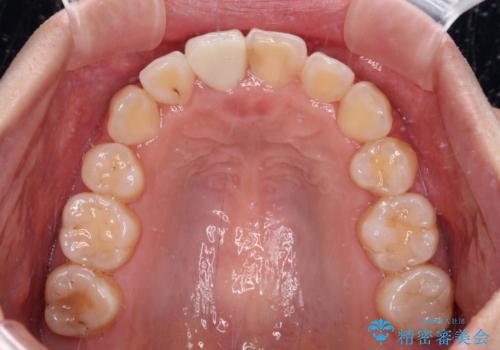

- 放置した虫歯や抜いたままの奥歯、前歯のデコボコを気にして来院された患者様です。

口元の突出感は少なく、下顎の叢生は軽微なものであったので、叢生の強い上顎左右の小臼歯を1本ずつ抜歯し、ワイヤー装置にて矯正治療を行うこととしました。

矯正治療を行う前に、根管治療の必要な上顎前歯と下顎大臼歯の根管治療を行い、矯正治療の途中で下顎の欠損部にインプラント埋入することとし、矯正治療後に補綴治療を行うこととしました。